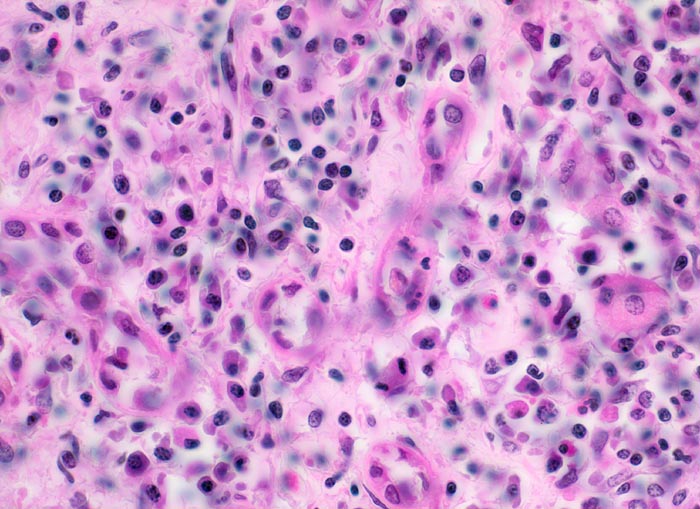

Morphologische Merkmale:

• Unauffällige Glomerula.

• Grössere intrarenale Arterien mit teils zirkulären, teils segmentalen, transmuralen fibrinoiden Gefässwandnekrosen und gemischtem transmuralem Entzündungsinfiltrat.

• Gefässveränderungen unterschiedlichen Alters (frische Nekrosen, Granulationsgewebsbildung, Narben).

• Frische Tubulusnekrosen (abgeblasste Kerne) im Versorgungsbereich der entzündeten Arterien.